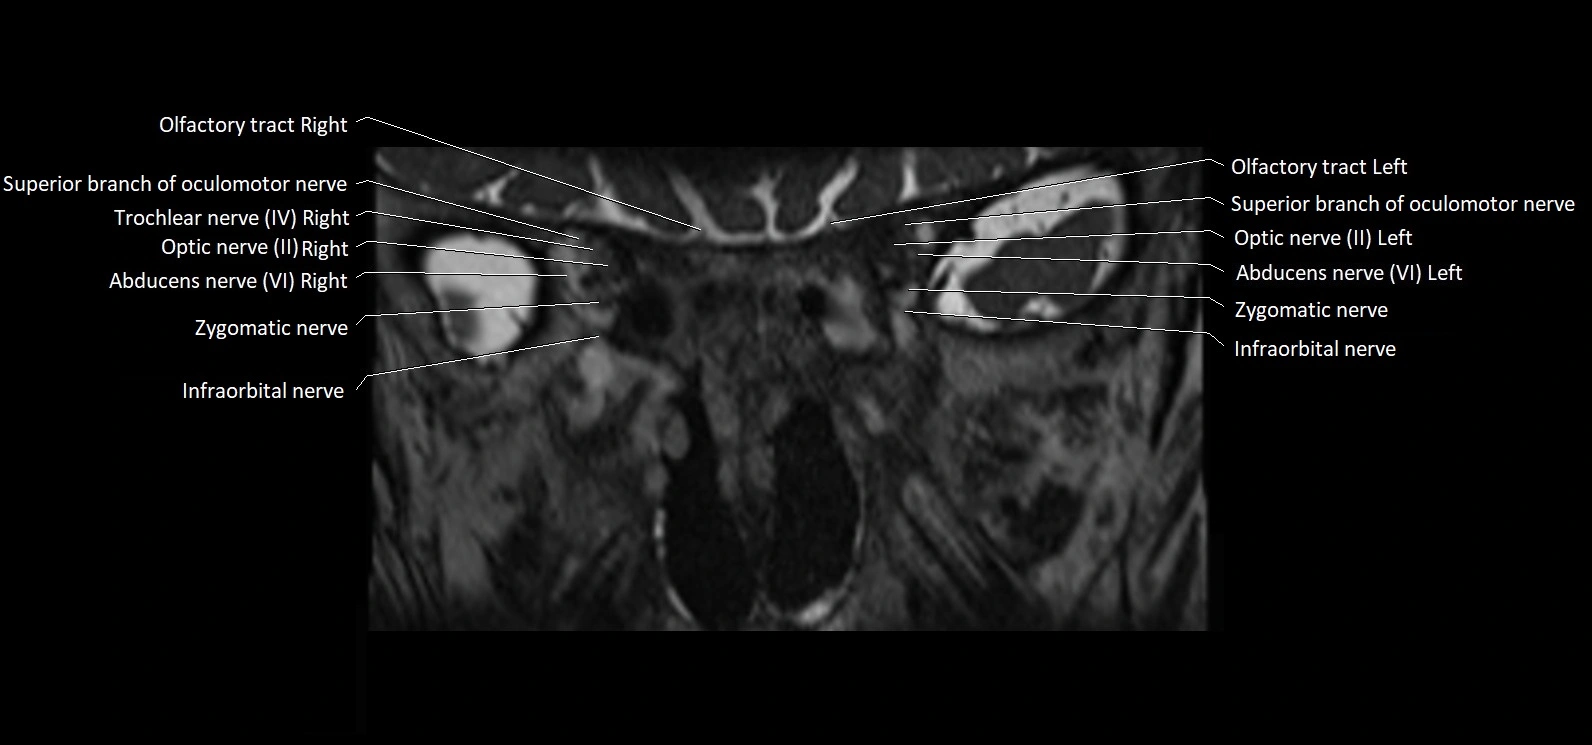

MRI images

image